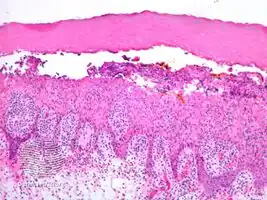

Infected keratocytes in skin swell and die.[2] The stain Lendrum’s phloxine tartazine, may be used to identify farmyard pox inclusion bodies.[2] Other tests include culture, fluorescent antibody test and electron microscopy.[2]

Cowpox, horsepox and smallpox may look similar and the histology may appear the same.[2]